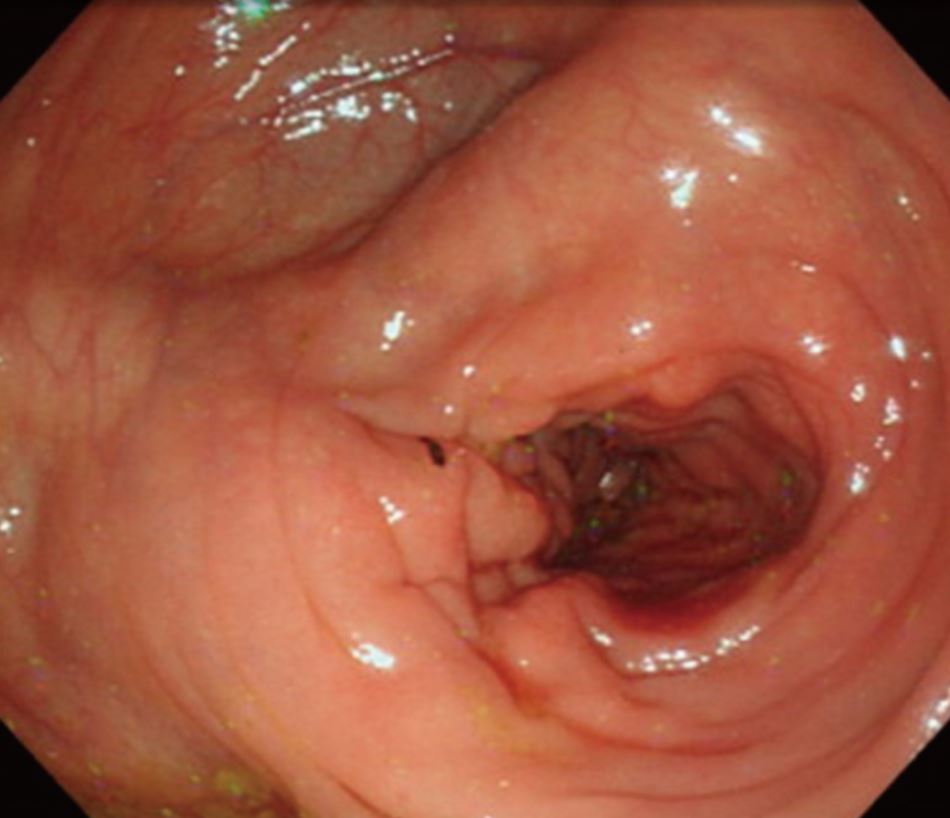

潰瘍性大腸炎と誤診され急激に悪化した大腸のDLBCLリンパ腫

最初の内視鏡と生検で「潰瘍性大腸炎」と診断されたが治療が全く効果が無く、2度目の内視鏡の生検でリンパ腫と診断。初発であり「長期経過の潰瘍性大腸炎に悪性リンパ腫が発生した」ものではなく「腸炎様のリンパ腫」であると結論している。過去に20件ほどの“colitis-like”

diffuse-type colorectal lymphomaの報告があるとのこと。